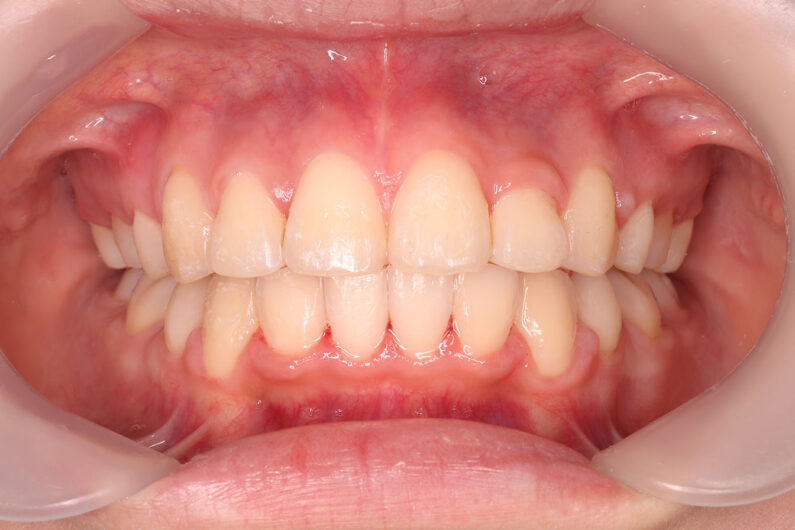

マルチブラケット 動的治療期間 3年5か月 調整回数29回

治療後は前歯は後退し、前歯の傾斜度も良くなっています。 口唇の緊張感も改善し、エステティックラインも綺麗になりました。